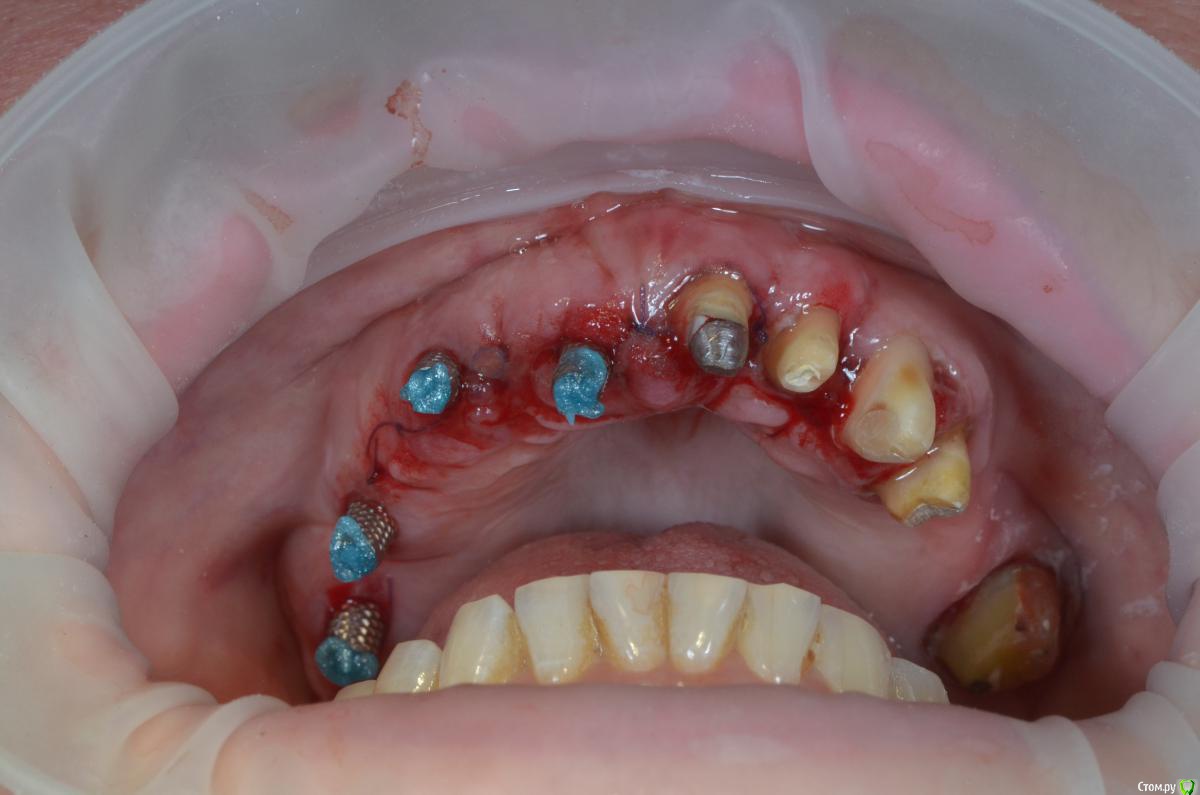

gangsta85 Опубликовано 22 декабря, 2018 Поделиться Опубликовано 22 декабря, 2018 Коллеги подскажите с тактикой протезирования?Есть проблема , хирург сильно укоротил зениты 21,22,23 .Работа с немедленной нагрузкой, торк 50н.Думаю сделать 2 фрезерованных моста с розовой десной, на зубы и имплантаты.благодарю) Ссылка на комментарий

Борис80 Опубликовано 24 декабря, 2018 Поделиться Опубликовано 24 декабря, 2018 (изменено) учитывайте, что положение импланта слишком вестибулярно, и десны больше 4 -5 мм получить от уровня кости нельзя, следовательно переустановив имплант вы лишите себя огромного количества проблем в будущем пока же сделайте временные коронки или более гладкими в области воспаления или более плотными к десне Изменено 24 декабря, 2018 пользователем Борис80 Ссылка на комментарий